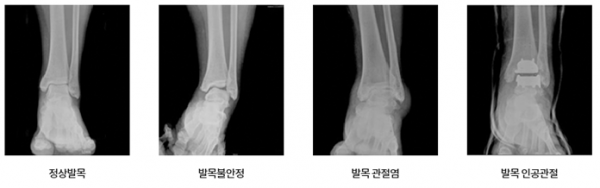

무릎에도 관절염이 있듯이 발목에도 관절염이 있습니다. 하지만 무릎이 퇴행성 관절염인 것과는 달리, 발목은 외상성 관절염이 많다는 차이가있습니다. 물론 발목에도 퇴행성 관절염이나 류머티스 관절염이 흔하게 발생합니다. 그러나, 발목 염좌나 발목 부위 골절의 후유증으로연골손상이 진행되는 경우에는 외상성 관절염이 발생합니다.